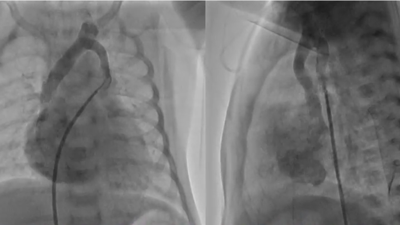

Fetal echocardiography was performed at 33 weeks of gestation at our institution, identifying a form of hypoplastic left heart syndrome with restrictive foramen ovale. The male infant was born at 38 weeks gestation via planned cesarean section, had an oxygen saturation of 89% on room air. A transthoracic echocardiography confirmed diagnosis of mitral stenosis, aortic stenosis, a small ventricular septal defect and restrictive foramen ovale (Fig. 1A–C). The four pulmonary veins were visualized, connecting to the left atrium. This patient was considered to be a candidate for the Fontan circulation in the future. Pulmonary congestion was not observed immediately after birth. We expected that pulmonary congestion should progress due to the restrictive inter-atrial communication when physiological pulmonary hypertension would decrease. This neonate underwent a balloon atrial septostomy at 1 day of age, followed by bilateral pulmonary artery banding at 2 days of age. Before performing the Norwood procedure, catheter investigation was carried out at 18 days old. This examination revealed step up of oxygen saturation at the superior vena cava; the oxygen saturation was 66%, 83%, and 93% at the inferior vena cava, the right atrium, and the superior vena cava respectively. We suspected a collateral vessel connecting the pulmonary vein to the systemic vein. Angiography of the left atrium revealed an abnormal vein draining to the innominate vein (Fig. 2A, Suppl Movie1). 3D contrast-enhanced computed tomography also showed this vein connecting the left pulmonary vein to the innominate vein (Fig. 2B, C). The abnormal vessel was identified as a levoatrial cardinal vein. The Norwood procedure was performed without ligation of this abnormal vessel. Enlargement of the atrial septal defect was performed simultaneously to avoid pulmonary congestion. The postoperative course was uneventful with no pulmonary venous obstruction.

Fig. 1 (A) Four-chamber view of the heart showing hypoplasia of the left atrium and the left ventricle. (B) Color-doppler imaging showing a small ventricular septal defect. The diameter of the defect is 2.37 mm. (C) Color-doppler imaging showing a small foramen ovale.

The diameter of the communication is 2.18 mm.